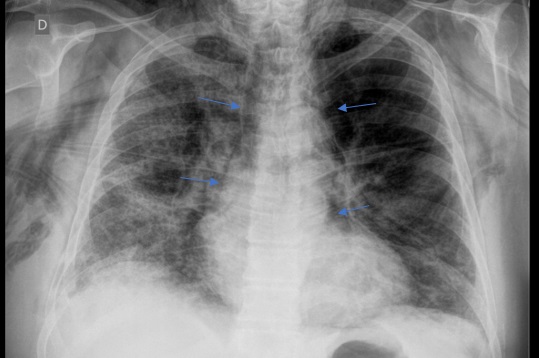

Dentro de los métodos diagnósticos, el neumomediastino se puede diagnosticar mediante radiografías o tomografía computada, donde se va a visualizar la presencia de aire (radiolucidez o hipodensidad lineales) rodeando las estructuras mediastinales. Un signo de muy alta especificidad es el llamado “signo del anillo alrededor de la arteria”, donde se visualiza una imagen radiolúcida o hipodensa en forma de anillo rodeando la arteria pulmonar, principalmente del lado derecho. Este signo ayuda a diferenciar esta entidad del neumopericardio, que puede verse similar en imágenes.

Among the diagnostic methods, pneumomediastinum can be diagnosed using X-rays or computed tomography scans, where the presence of air (linear radiolucency or hypodensity) surrounding the mediastinal structures will be visualized. A highly specific sign is the so-called “ring sign around the artery”, where a radiolucent or hypodense ring-shaped image is visualized surrounding the pulmonary artery, primarily on the right side. This sign helps differentiate this condition from pneumopericardium, which can appear similar on imaging.